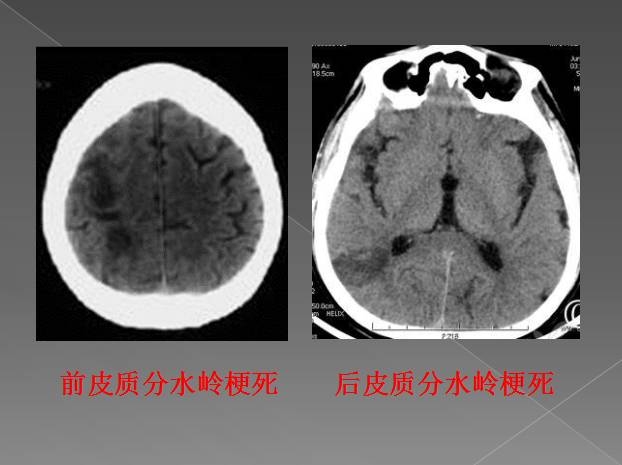

根据供血区域不同,分水岭脑梗分为三型:

皮质前型

大脑前与大脑中动脉供血区的分水岭脑梗死,位于额中回,呈带状或楔形。临床表现为以上肢为主的中枢性偏瘫及偏身感觉障碍,一般无面舌瘫,可有情感障碍、强握反射和局灶性癫痫。主侧病变可出现经皮层性运动性失语,双侧病变出现四肢瘫及智能障碍或痴呆等。

皮质后型

大脑中与大脑后动脉或大脑前中后动脉皮层支间的分水岭区。病灶位于顶枕颞交界区,以偏盲最常见,多以下象限盲为主。皮质性感觉障碍偏瘫轻微或无,约1/2病例有情感淡漠,可有记忆力减退,主侧病变出现认字困难和经皮层感觉性失语,非主侧偶见体象障碍。

另外,还有浅表型和深部型之分。该病的诊断并不困难,通过颅脑CT和颅脑核磁共振检查,很容易做出诊断。